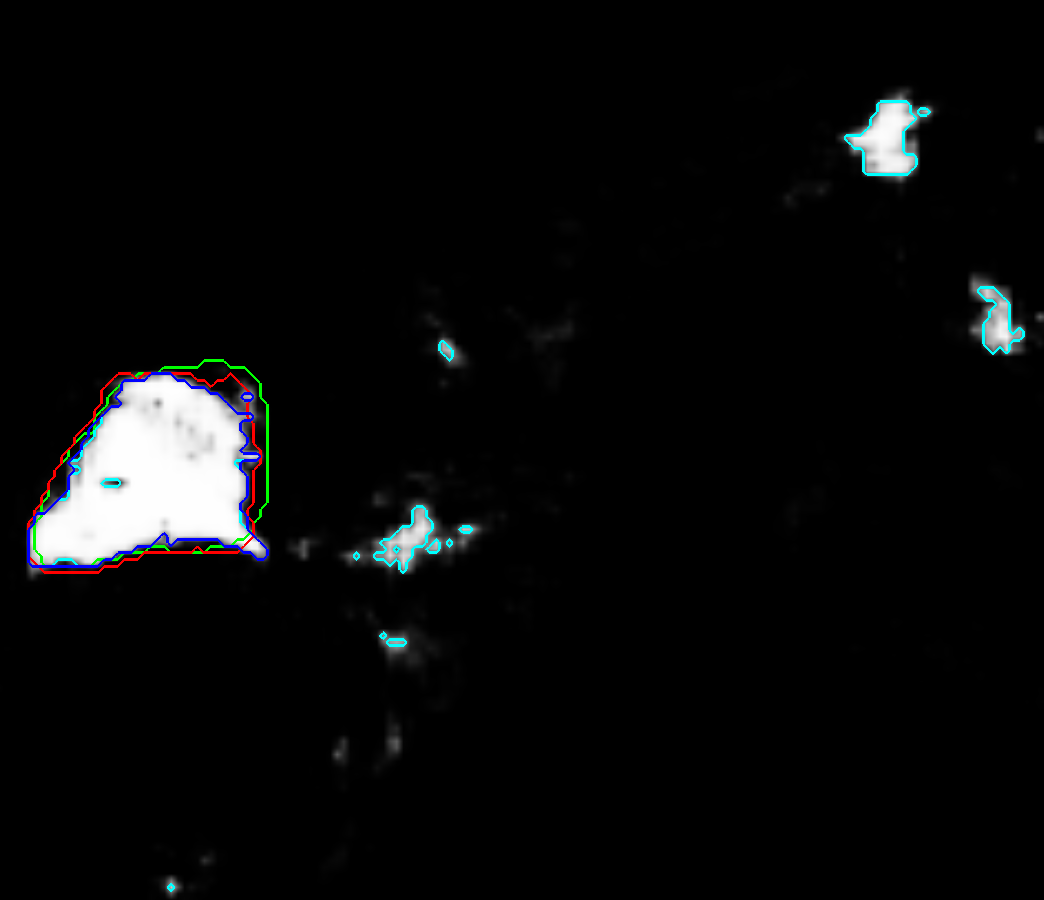

Refer to caption a) CT Refer to caption b) CNN prior Refer to caption c) Intensity based prior Refer to caption d) ACM distance map

Refer to caption e) CT Refer to caption f) CNN prior Refer to caption g) Intensity based prior Refer to caption h) ACM distance map

Refer to caption i) CT Refer to caption j) CNN prior Refer to caption k) Intensity based prior Refer to caption l) ACM distance map

Figure 2: RW input images with reference contour (green), RW contour (red), CNN with 50 % threshold (cyan) and CNN with 50 % threshold and morphological closing (blue): first column depicts CT slices; second and third column show the probabilities generated by the CNN and the intensity prior model, respectively; the distance maps generated with the ACM are shown in the fourth colulmn. Figures a - d) show public case 27, e - f) depict public case 01 and i - l) show clinical case 20.